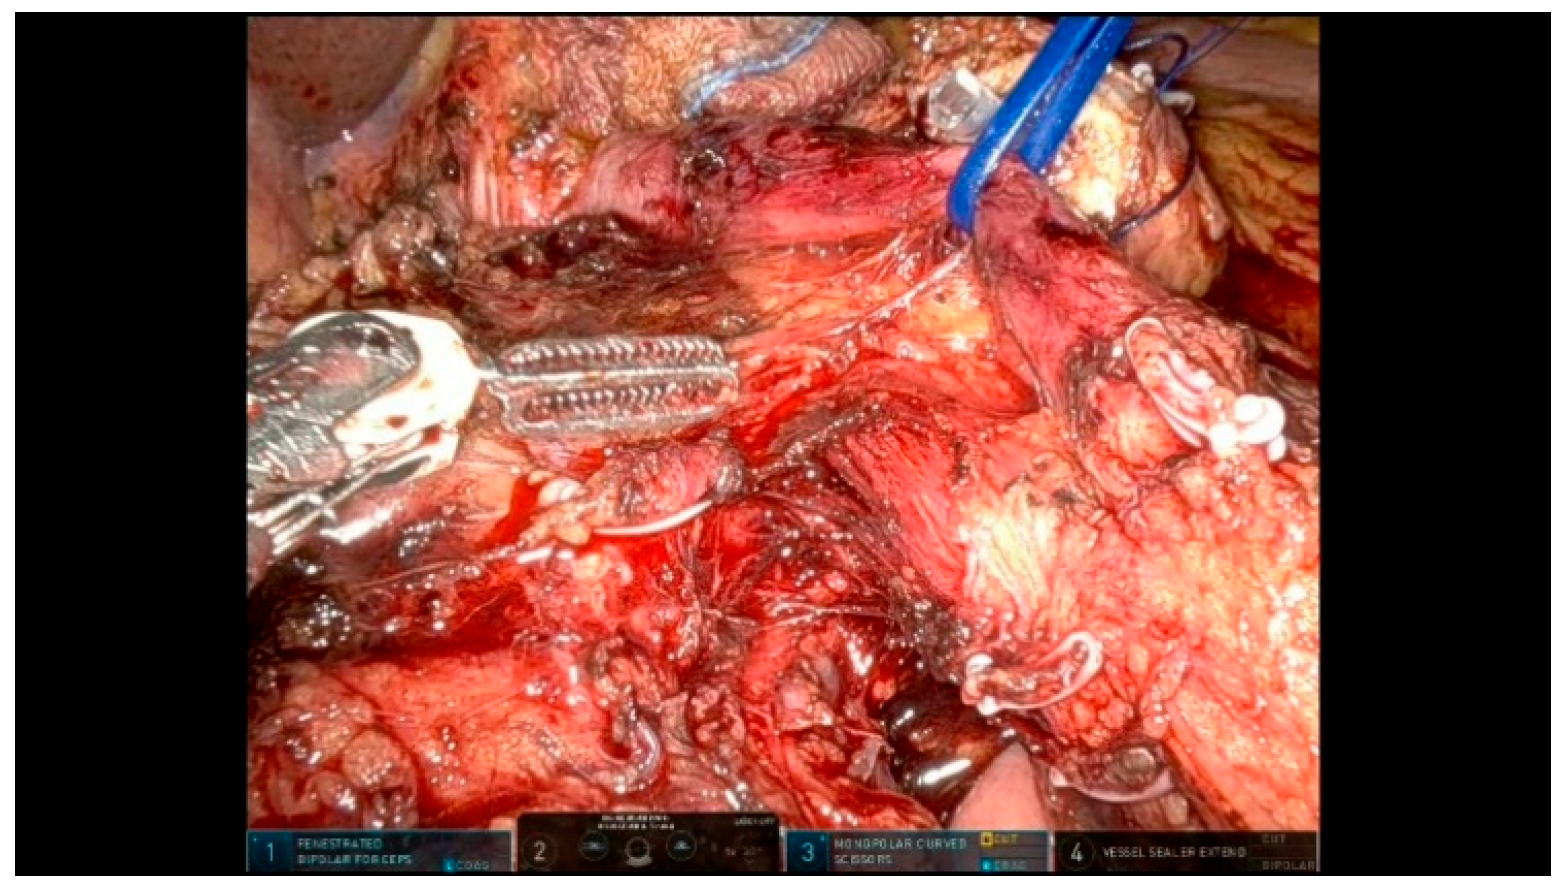

3.2.2. Step 12: Hepaticojejunostomy